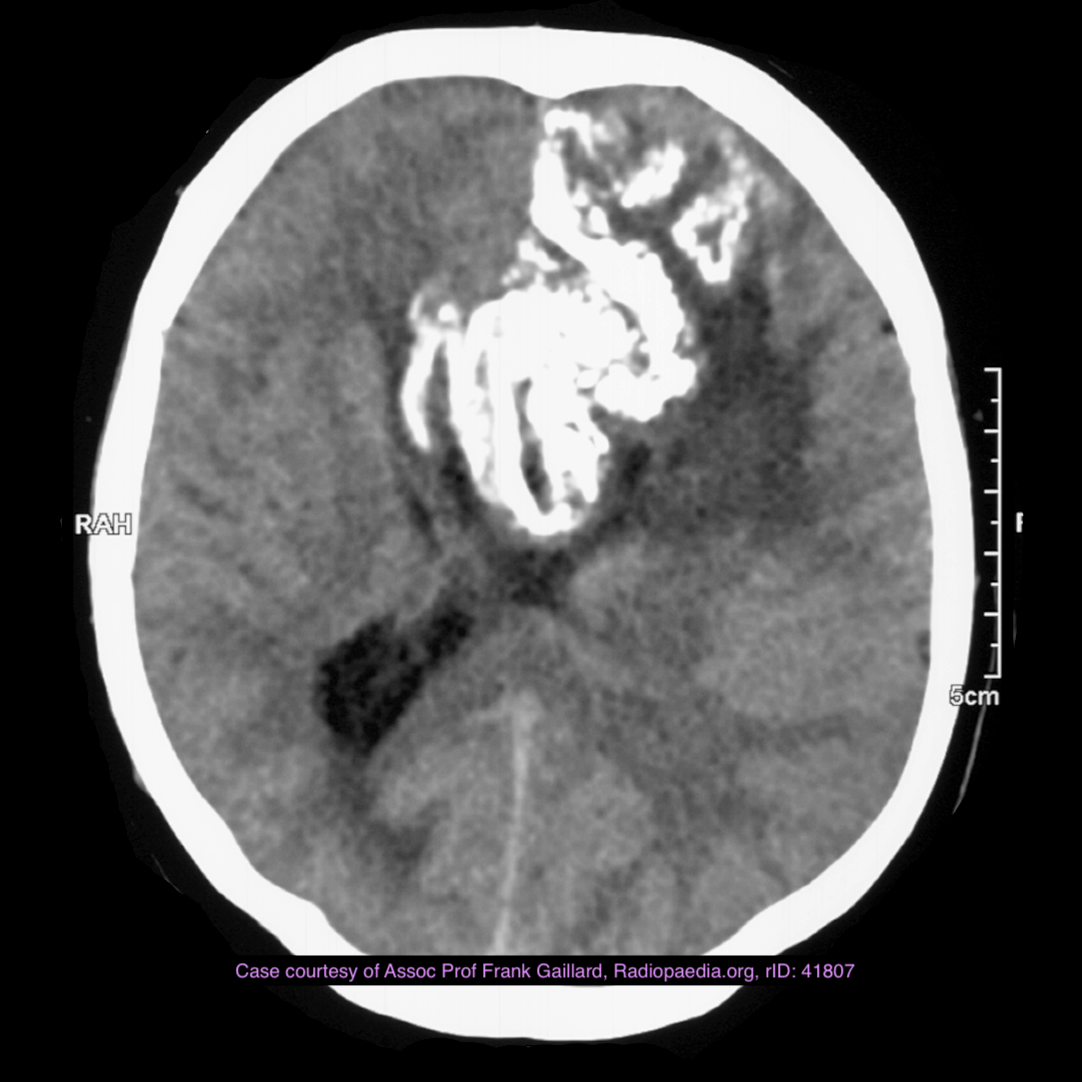

Note the multiple sites of oedema and haemorrhage, involving the brain stem and corpus callosum as well as subcortical white matter and left cerebral peduncle. High FLAIR signal is also seen in the dorsal midbrain. EVD insitu.

Case Discussion

Diffuse axonal injury can be subtle on CT but have devastating consequences for the patient. This is a case of grade III injury (involvement of brainstem) and carries a poor prognosis.

Diffuse axonal injury (DAI), also known as traumatic axonal injury (TAI), is a severe form of traumatic brain injury due to shearing forces. It is a potentially difficult diagnosis to make on imaging alone, especially on CT as the finding can be subtle, however, it has the potential to result in severe neurological impairment.

The diagnosis is best made on MRI where it is characterised by several small regions of susceptibility artifact at the grey-white matter junction, in the corpus callosum, and in more severe cases in the brainstem, surrounded by FLAIR hyperintensity.

Diffuse axonal injury is characterised by multiple focal lesions with a characteristic distribution: typically located at the grey-white matter junction, in the corpus callosum and in more severe cases in the brainstem (see: grading of diffuse axonal injury).

CT

Non-contrast CT of the brain is routine in patients presenting with head injuries. Unfortunately, it is not sensitive to subtle diffuse axonal injury and as such, some patients with relatively normal CT scans may have significant unexplained neurological deficit 4,5.

The appearance depends on whether or not the lesions are overtly haemorrhagic. Haemorrhagic lesions will be hyperdense and range in size from a few millimetres to a few centimetres in diameter. Non-haemorrhagic lesions are hypodense. They typically become more evident over the first few days as oedema develops around them. They may be associated with significant and disproportionate cerebral swelling.

CT is particularly insensitive to non-haemorrhagic lesions (as defined by CT) only able to detect 19% of such lesions, compared to 92% using T2 weighted imaging 4. When lesions are haemorrhagic, and especially when they are large, then CT is quite sensitive. As such, it is usually a safe assumption that if a couple of small haemorrhagic lesions are visible on CT, the degree of damage is much greater.